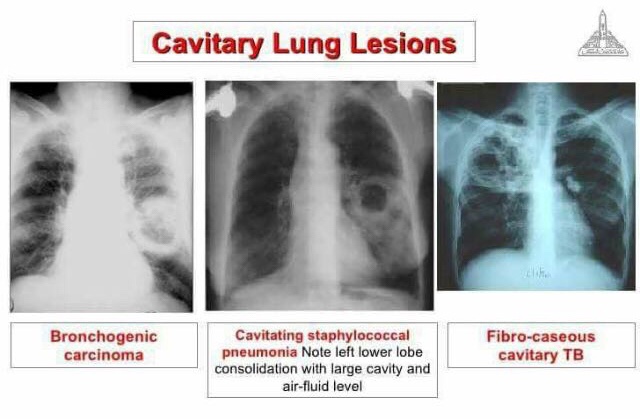

3) CAVITARY LUNG LESIONS

X-Ray shows Ring shadows👇🏻

- Thick walled – Lung Abscess, Bronchogenic Carcinoma

- Thin shaggy walled – Tuberculosis, Lung Abscess, Bronchogenic Carcinoma

- Thin smooth walled – Tuberculosis, Bullae

Percussion: Crack pot sound (Empty)